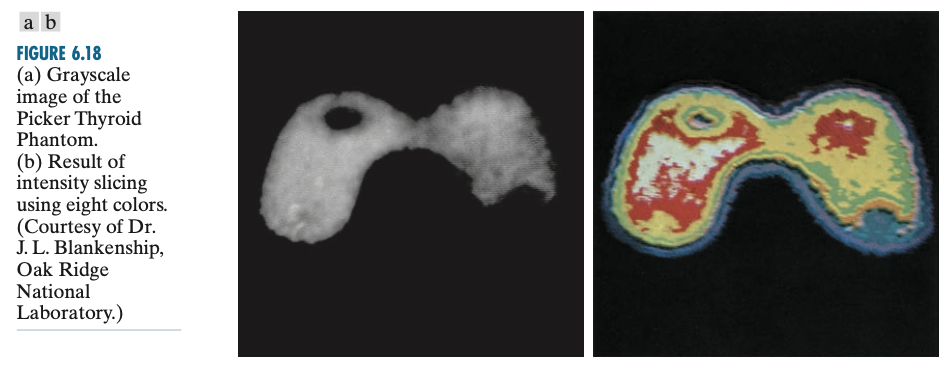

여기서 $c_{k}$는 $l = k - 1$과 $l = k$에 있는 분할 평면들에 의해 정의되는 $k$번째 밝기 구간 $V_{k}$와 관련된 칼라가 됩니다. 이를 이용하면 아래의 그림과 같이 표현할 수 있습니다.

왼쪽의 그림에서는 왼쪽 부분과 오른쪽 부분이 그리 큰 차이가 나지 않는 것 같지만 오른쪽 그림을 보면 왼쪽 부분의 밝기가 좀 더 강한 것을 볼 수 있습니다.